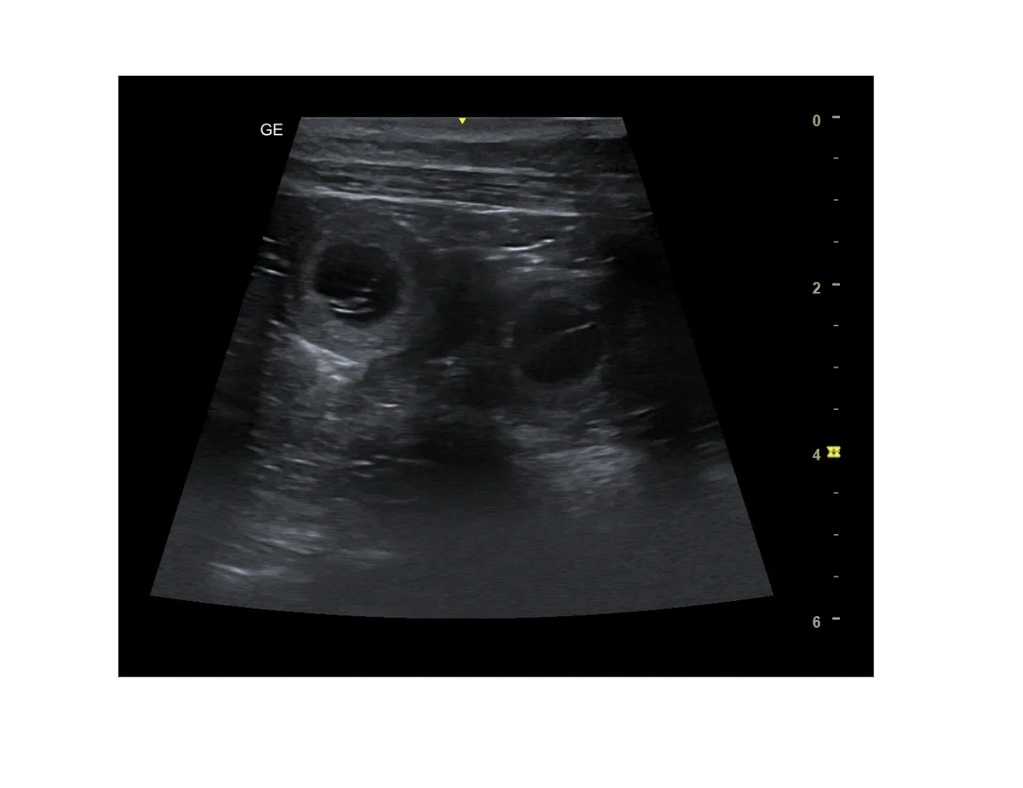

Heute waren wir beim Ultraschall .Wie gehofft ist Ayla tragend ,ihr gehts prima .Noch sieht man ihr äußerlich nichts an ,dass wird sich aber bald ändern

Wir haben einige Fruchthüllen gesehen die sich gleichmäßig in den Gebärmutter Hörnern verteilt haben